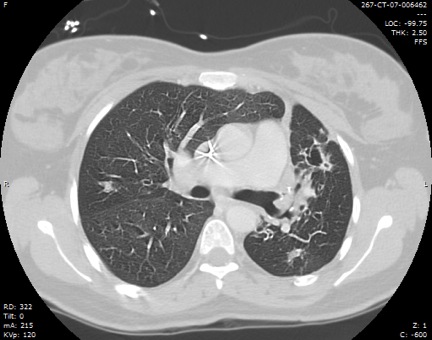

Figure 2: Chest computed tomography showing bronchiectasis and right upper lobe opacity suggesting the site of bleed